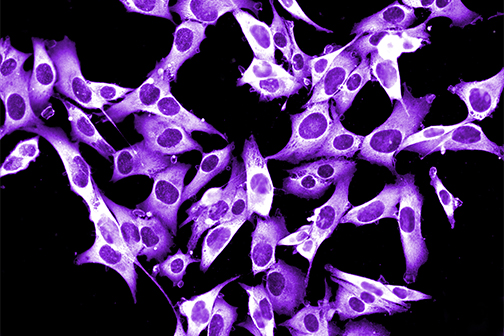

LSU Health New Orleans Develops New Human Cell Line to Study Blinding Eye Disorders

Under the direction of Boyd Professor Nicolas Bazan, MD, PhD, scientists at LSU Health New Orleans Neuroscience Center of Excellence have developed a new, experimental human cell line from retinal pigment epithelial cells. Called ABC, these cells so closely resemble and retain the properties of native retinal pigment epithelial (RPE) cells, the research team has shown that they are a reliable cell system to study retinal degenerative diseases. More